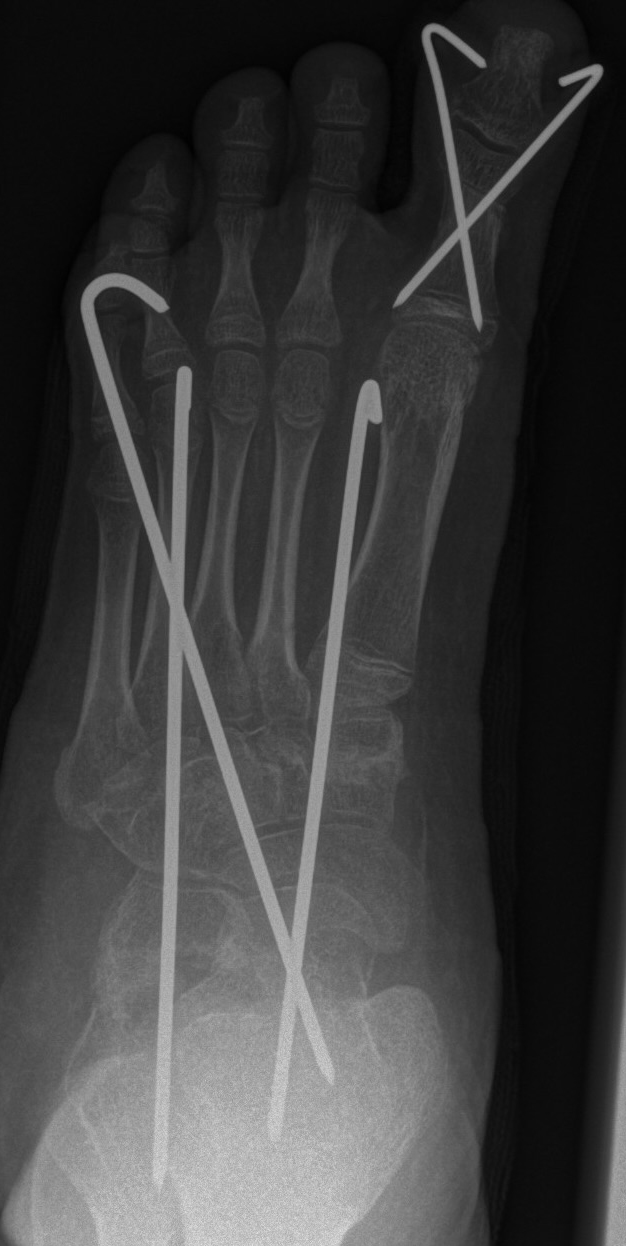

Zusätzlich schränken Wachstumsfugen die Wahl der Osteosynthese ein. Eine die Fuge kreuzende Osteosynthese ist ausschließlich mit Kirschner-Drähten möglich (Abb. 3).

Abb. 3 a-j: Beispiel einer Calcaneusverschiebeosteotomie mit offenen Wachstumsfugen und der entsprechenden Osteosynthese mit Kirschner Drähten. Lokalisation der Osteotomie (a), Lage der Fräse (b-d), Drahtlage mehrere Ansichten (e-h), Heilung der Osteotomie 4 Wochen postoperativ und Entfernung der Drähte (i-j).

Calcaneus-Osteotomie

Die minimalinvasive Calcaneusverschiebeosteotomie bietet eindeutige Vorteile gegenüber dem offenen Verfahren, sodass wir bei Kindern und Jugendlichen nahezu keine offene Verschiebeosteotomie mehr durchführen. Am Calcaneus liegt die offene Wachstumsfuge dorsal. Bei der Durchführung müssen Schenkel der V-förmigen Osteotomie daher etwas steiler angelegt werden, in einem stumpfen Winkel (siehe Abb. 3 a-j). Für die Osteotomie liegen unsere Patienten auf dem Rücken und der BV wird für die exakte Seitaufnahme eingestellt. Der Fuß lagert auf einem hohen OP-Kissen und die Osteotomie kann bequem mit einem langen Kirschner-Draht und einem sterilen Stift angezeichnet werden (Abb. 15).